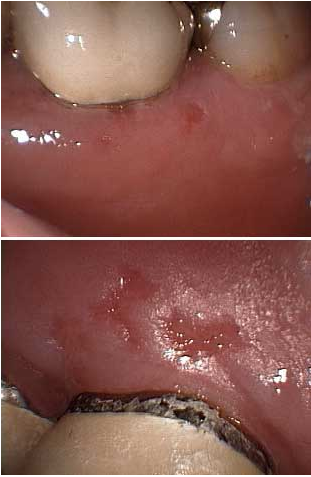

Erythroplakia

Erythroplakia is a red plaque that is a tissue lesion characterized by thickened epithelial mucosa with areas of white plaques.

Erythroplakia is also known as vascularized leukoplakias.

Red plaques are associated with oral cancer.

Erythroplakia usually occurs on the gingiva, buccal mucosa, lateral tongue surface, floor of mouth or retromolar trigone.

These lesions are most commonly found on the anterior surface of the maxillary alveolar ridge, but they have been reported to arise on the hard palate, vestibular sulcus and soft palate.